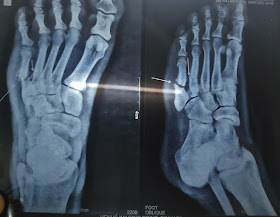

Then 18 yrs later (I.e 3 yrs ago) he was on a morning walk where because of darkness he couldn't see and fell down again and was taken to orthopedic where on x rays he was found to be having a fracture on the 5th metatarsal and he was advised for an open reduction but the patient denied surgery because of his financial condition and so was given tablets. According to patient he was able to walk during the time he had fracture and would continue doing his work with reduced workload. He could not dorsi flex his leg.After 4-5 months of this episode and a serial x rays his fractured appeared healed.